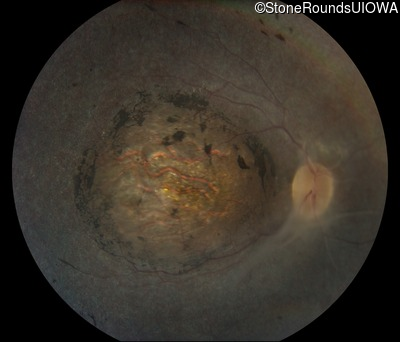

Fundus Photography - Left - Light Perception

Exemplar